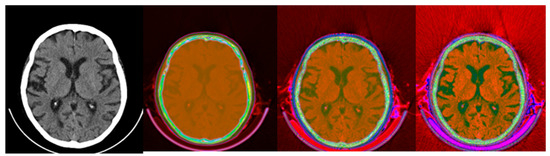

2.2. Method 1: Colormap Information Transform (CIT)

3.1. CIT Application

3.2. Colormap Folding Application